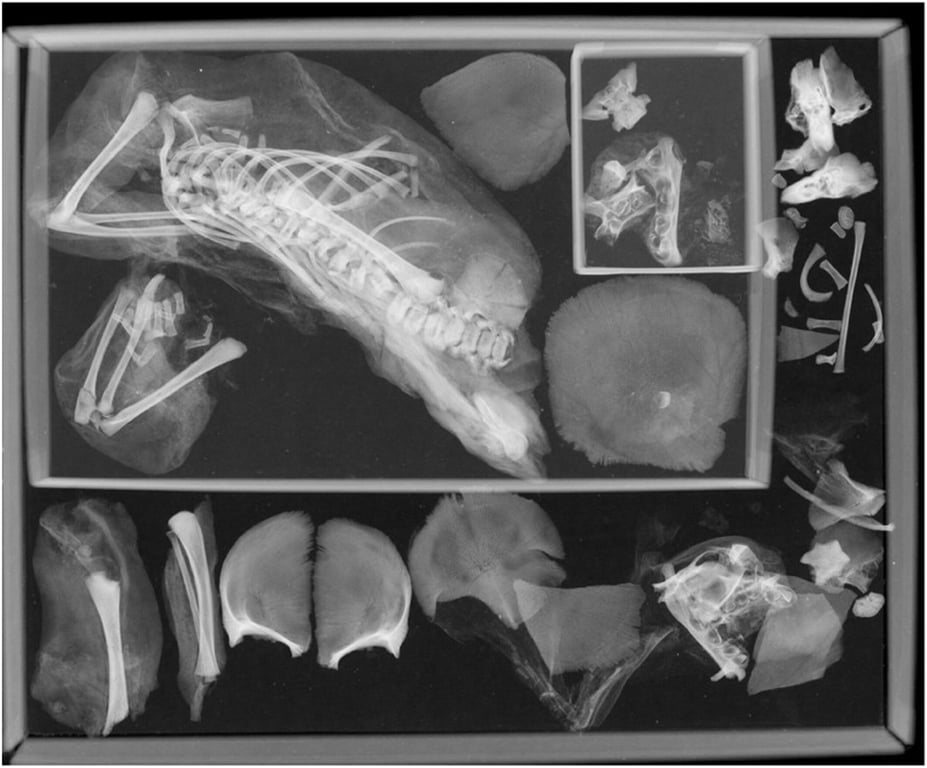

Плівкова рентгенограма муміфікованого плоду. Фото: wileyonlinelibrary.com

На фото нижче стрілка вказує на залишки за межами грудної порожнини, розміщені в муміфікованій тканині. Коло вказує на череп плода, ребра та довгі кістки. Далі рентгенівський знімок грудної порожнини жіночої мумії. Зверніть увагу на кістки плоду, включаючи нервову дугу та п’ясткову кістку, які мігрували за межі грудної порожнини (стрілка), і залишки плоду в лівій грудній порожнині (коло):

КТ та рентген мумії. Фото: wileyonlinelibrary.com